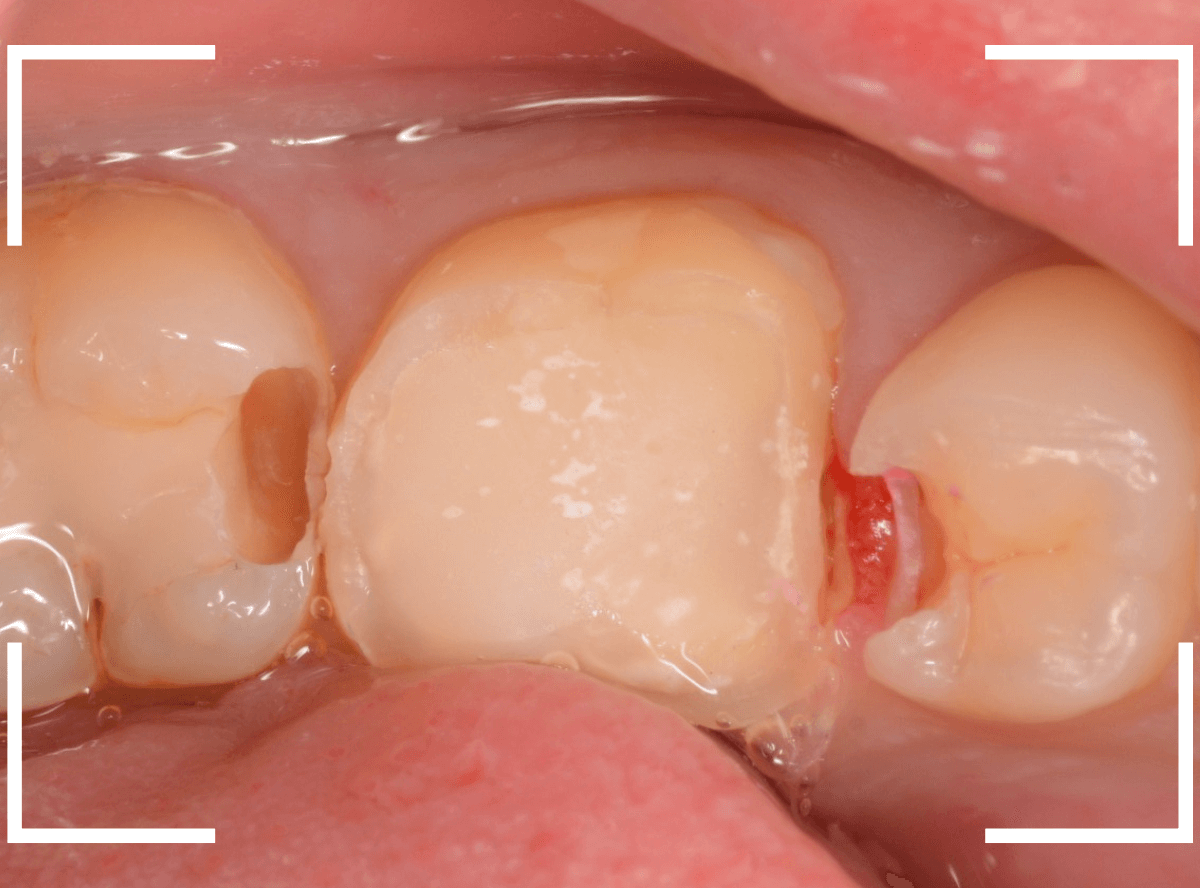

まず、土台の治療をしてから時間が経過していることと、不適合になっている事から、外して中を調べます。

すると、土台の中で虫歯にもなっていました。

(〇部の赤い部分)

こういった事は、レントゲン写真でもよくわからない事が多く、土台を外す治療は本当に神経を使います。

今回は、歯肉の中まで歯が欠損しているので、このまま土台とさし歯を作り直しても、いい結果にはなりません。

患者さんに状況を説明し、歯の周りの歯肉を麻酔をして電気メスでトリミングします。

このように歯の際が歯肉からしっかり出てる状況で製作しないと、さし歯はしっかりお口の中で安定しません。